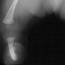

PHYSICAL EXAM: Examination of the right lower extremity demonstrates shortening of the right thigh with a 10 degree flexion contracture present in the knee. The knee is noted to be in valgus. There is moderate anteromedial bowing present in the leg with a dimple present over the anterior aspect of the tibia at the apex of the bow. The foot is held in a position of severe equinovalgus with absence of the lateral two rays noted. There is syndactyly present among the remaining digits. Circulation is normal and skin condition is good. Overall, the right lower extremity is noted to be 5 cm. shortened when compared to the contralateral normal extremity. Attempts at ambulation were limited by the severe deformity present in the right lower extremity.

RADIOGRAPHS: Absent right fibula and lateral two rays of right foot with moderate anteromedial bowing of tibia. The right femur was also noted to be shortened.